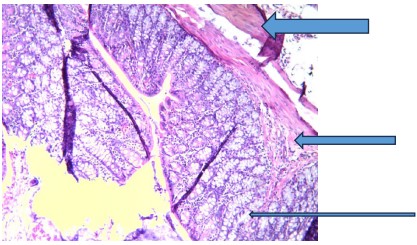

Sections of the colon tissues of rats exposed to 1,2-dimethylhydrazine revealed inflamed colon mucosa and tumor development in the colon when compared with control, which displayed normal mucosa (very thin arrow) consisting of columnar epithelium, lamina propria, and muscularis mucosa (Fig. 1). Also, the underlying submucosa (thin arrow) and muscularis propria (thick arrow) are essentially normal.

The irregularities detected in the DMH group, as shown in Fig. 2, are due to increased cell proliferation, apoptosis, and the formation of preneoplastic lesions and tumors18. Consequently, segments of colon tissues of rats administered V. amygdalina alone or before and after DMH induction revealed mild to moderate recovery from early signs of colon tumorigenesis, followed by reduced inflammatory cell infiltration as shown in Fig. 3-8, respectively. This suggests that the extract can improve colon histoarchitecture deformities because of its protective effects, which are characterized by bioactive components like flavonoids, saponins, and polyphenols present in it19.